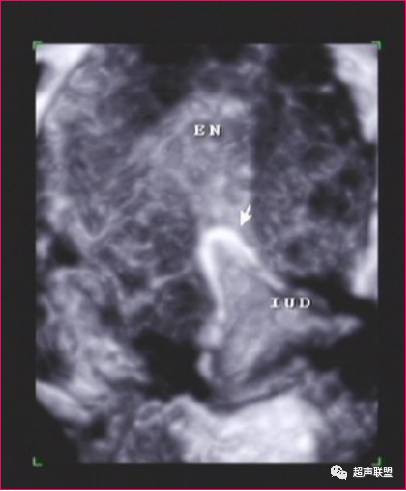

IUD合并妊娠

在子宫内显示妊娠囊与IUD的回声同时存在,可诊断为IUD合并宫内妊娠(带器妊娠)。超声诊断带器妊娠的价值在于能清晰的显示子宫、IUD和妊娠囊,以及三者的关系。

声像图特征:

1、子宫增大,增大的径值与孕周成正比。

2、早期妊娠时,在子宫腔内显示完整的妊娠囊,随妊娠周数的增加,囊内可见到胎芽、原始心管搏动及胎动。在妊娠囊的下方、侧方、上方或接近子宫颈口处,显示强回声的IUD,由于妊娠囊暗区的衬托,IUD回声显示格外清楚。